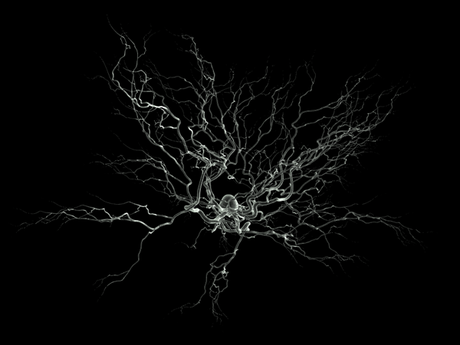

Imagen artística de una neurona en el microscopio electrónico de barrido. El corazón de la neurona se encuentra en el centro, mientras que los filamentos permiten las conexiones con las células vecinas. © 2003 Nicolas P. Rougier, Wikipedia, GNU